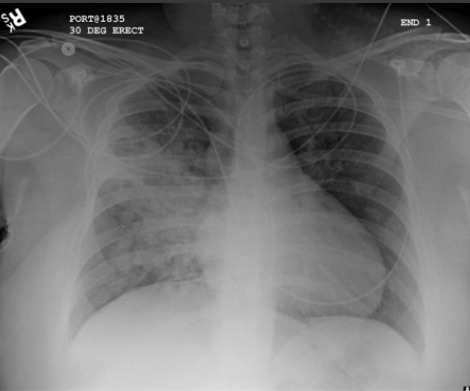

Opacificação aumentada da região peri-hilar direita e do segmento superior dos lobos inferior e superior direitos, compatível com agravamento da pneumonia por aspiração

Da coleção do Dr. Roy Hammond. Usado com permissão